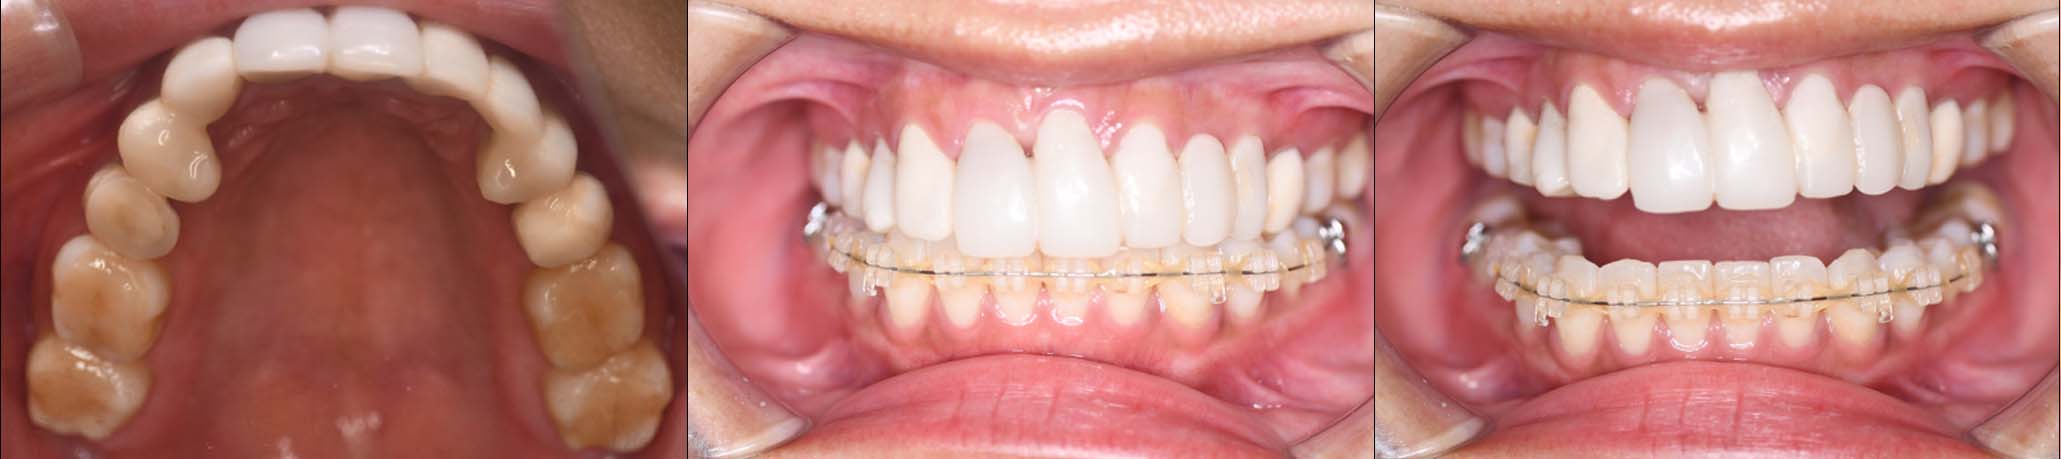

| 治療内容 | ①スプリントを装着 ②副子を装着 ③2024年4月 口腔内反映開始 ④副子を入れた状態の所まで咬合を挙上 (バイトアップ) ⑤2024年5月 上顎前歯部8本に仮歯(TEK) を装着 |

2月20日

3月13日

4月24日

9月25日